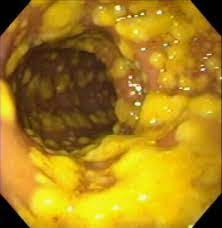

C.Difficiale değişik 2 toksin (toksin A ve B) salgılar, bunlarda bağırsak mukozasında tahribat yaparak ishale neden olur. Dışkıda bunların varlığının gösterilmesi ile tanı konur. %25 vakada tanı konmayabilir. Gaitada bu toksinlerin gösterilememesi hastalığın olmadığını göstermez. Kolonoskopide kalın bağırsak mukozasında psödomembran adı verilen sarı renkli plakların olması tanıya yardımcıdır.